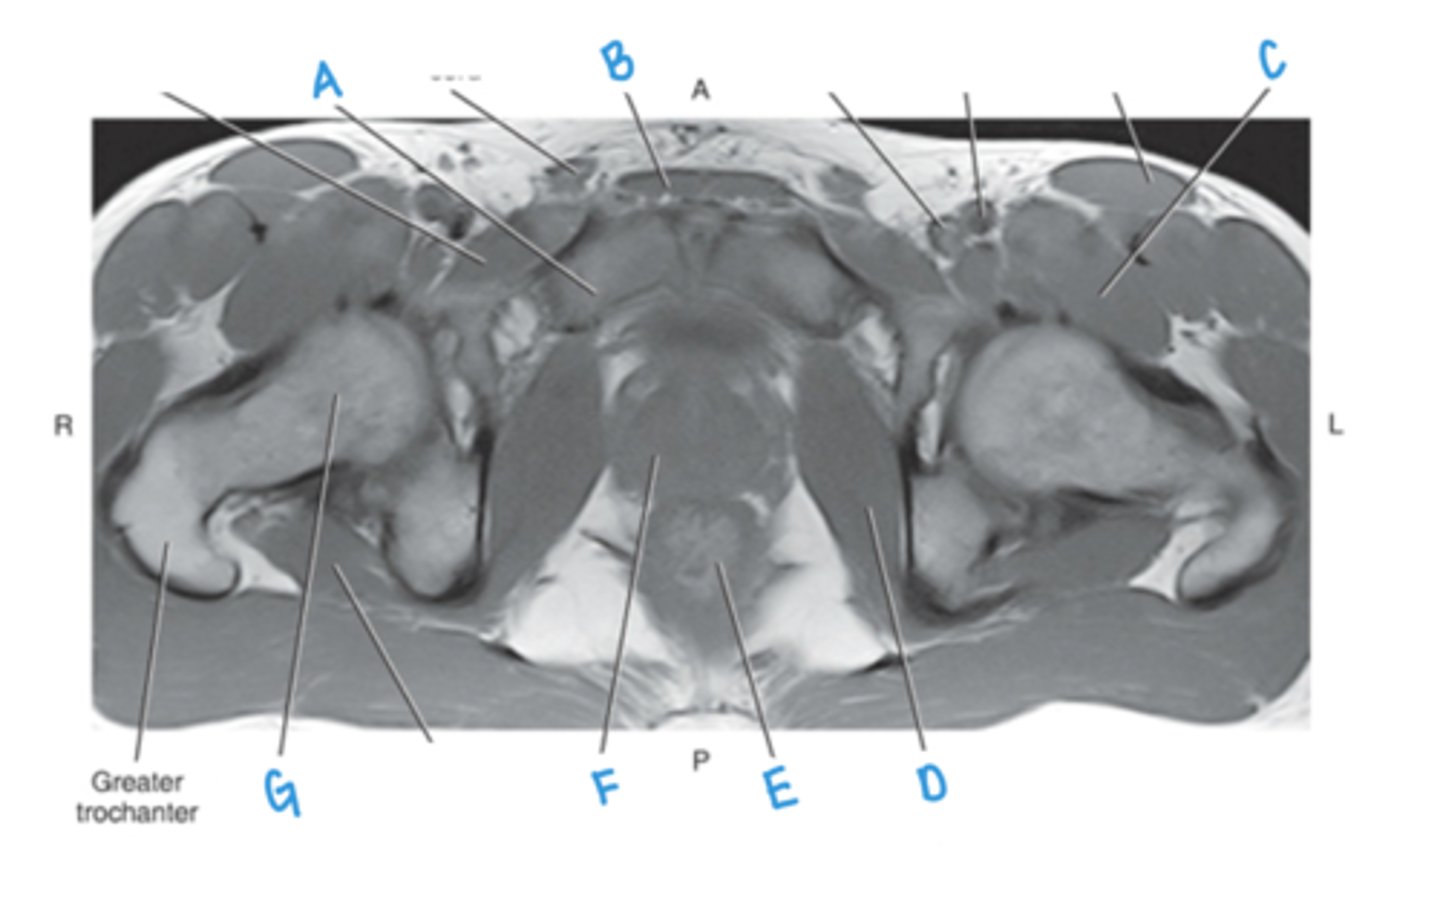

superior pubic ramus

A

rectus abdominus muscle

B

iliopsoas muscle

C

obturator internus muscle

D

rectum

E